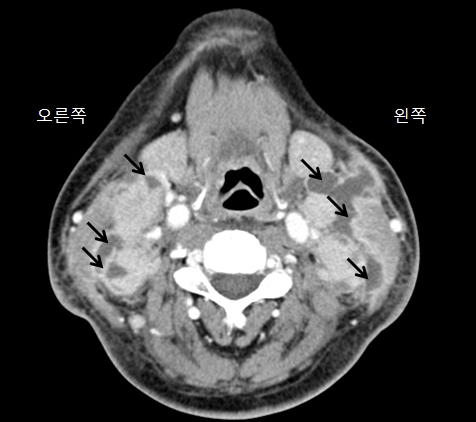

경부 림프절염(Cervical lymphadenitis)

- 증상

-

통증 없는 부종,

압통,

열

- 관련질환

풍진,

홍역,

아데노이드의 비대를 동반한 편도의 비대,

결핵성 임파선염,

림프관종,

림프종,

임파선염,

이하선염,

편도선염,

림프부종

- 진료과

감염내과,

이비인후과